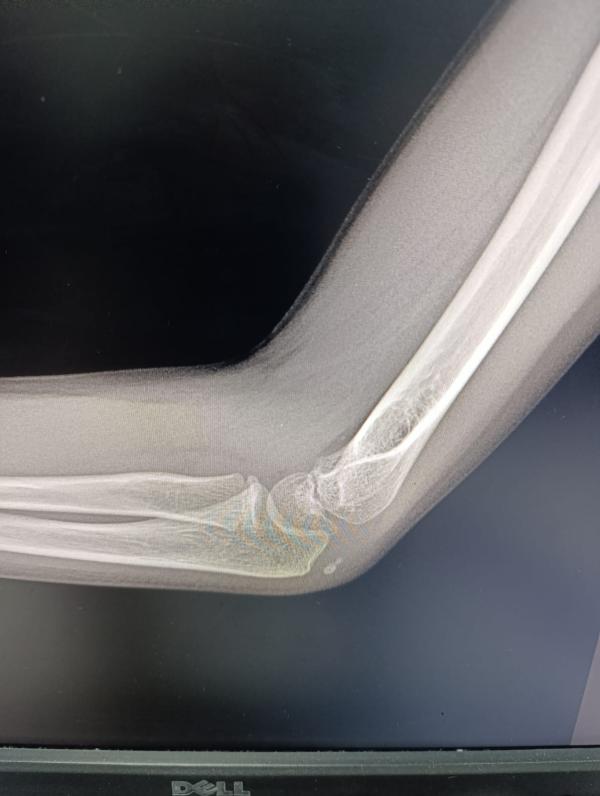

post image 1

Сыну сделали снимок, но врача нет . Врач будет завтра. Может кто увидит и подскажет, есть перелом или что-то такое, или нет.

Сын вчера упал на локоть, жалуется что болит

Трещина и осколок, правильно вам написали

И еще и осколок похоже 🤷🏻‍♀️